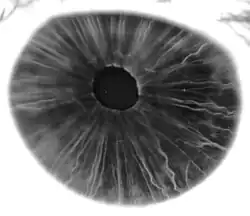

The iris (pl.: irides or irises) is a thin, annular structure in the eye in most mammals and birds that is responsible for controlling the diameter and size of the pupil, and thus the amount of light reaching the retina. In optical terms, the pupil is the eye's aperture, while the iris is the diaphragm. Eye color is defined by the iris.

The iris consists of two layers: the front pigmented fibrovascular layer known as a stroma and, behind the stroma, pigmented epithelial cells.

Eye color

Iris color is a highly complex phenomenon consisting of the combined effects of texture, pigmentation, fibrous tissue, and blood vessels within the iris stroma, which together make up an individual's epigenetic constitution in this context.[4] An organism's "eye color" is actually the color of one's iris, the cornea being transparent and the white sclera entirely outside the area of interest.